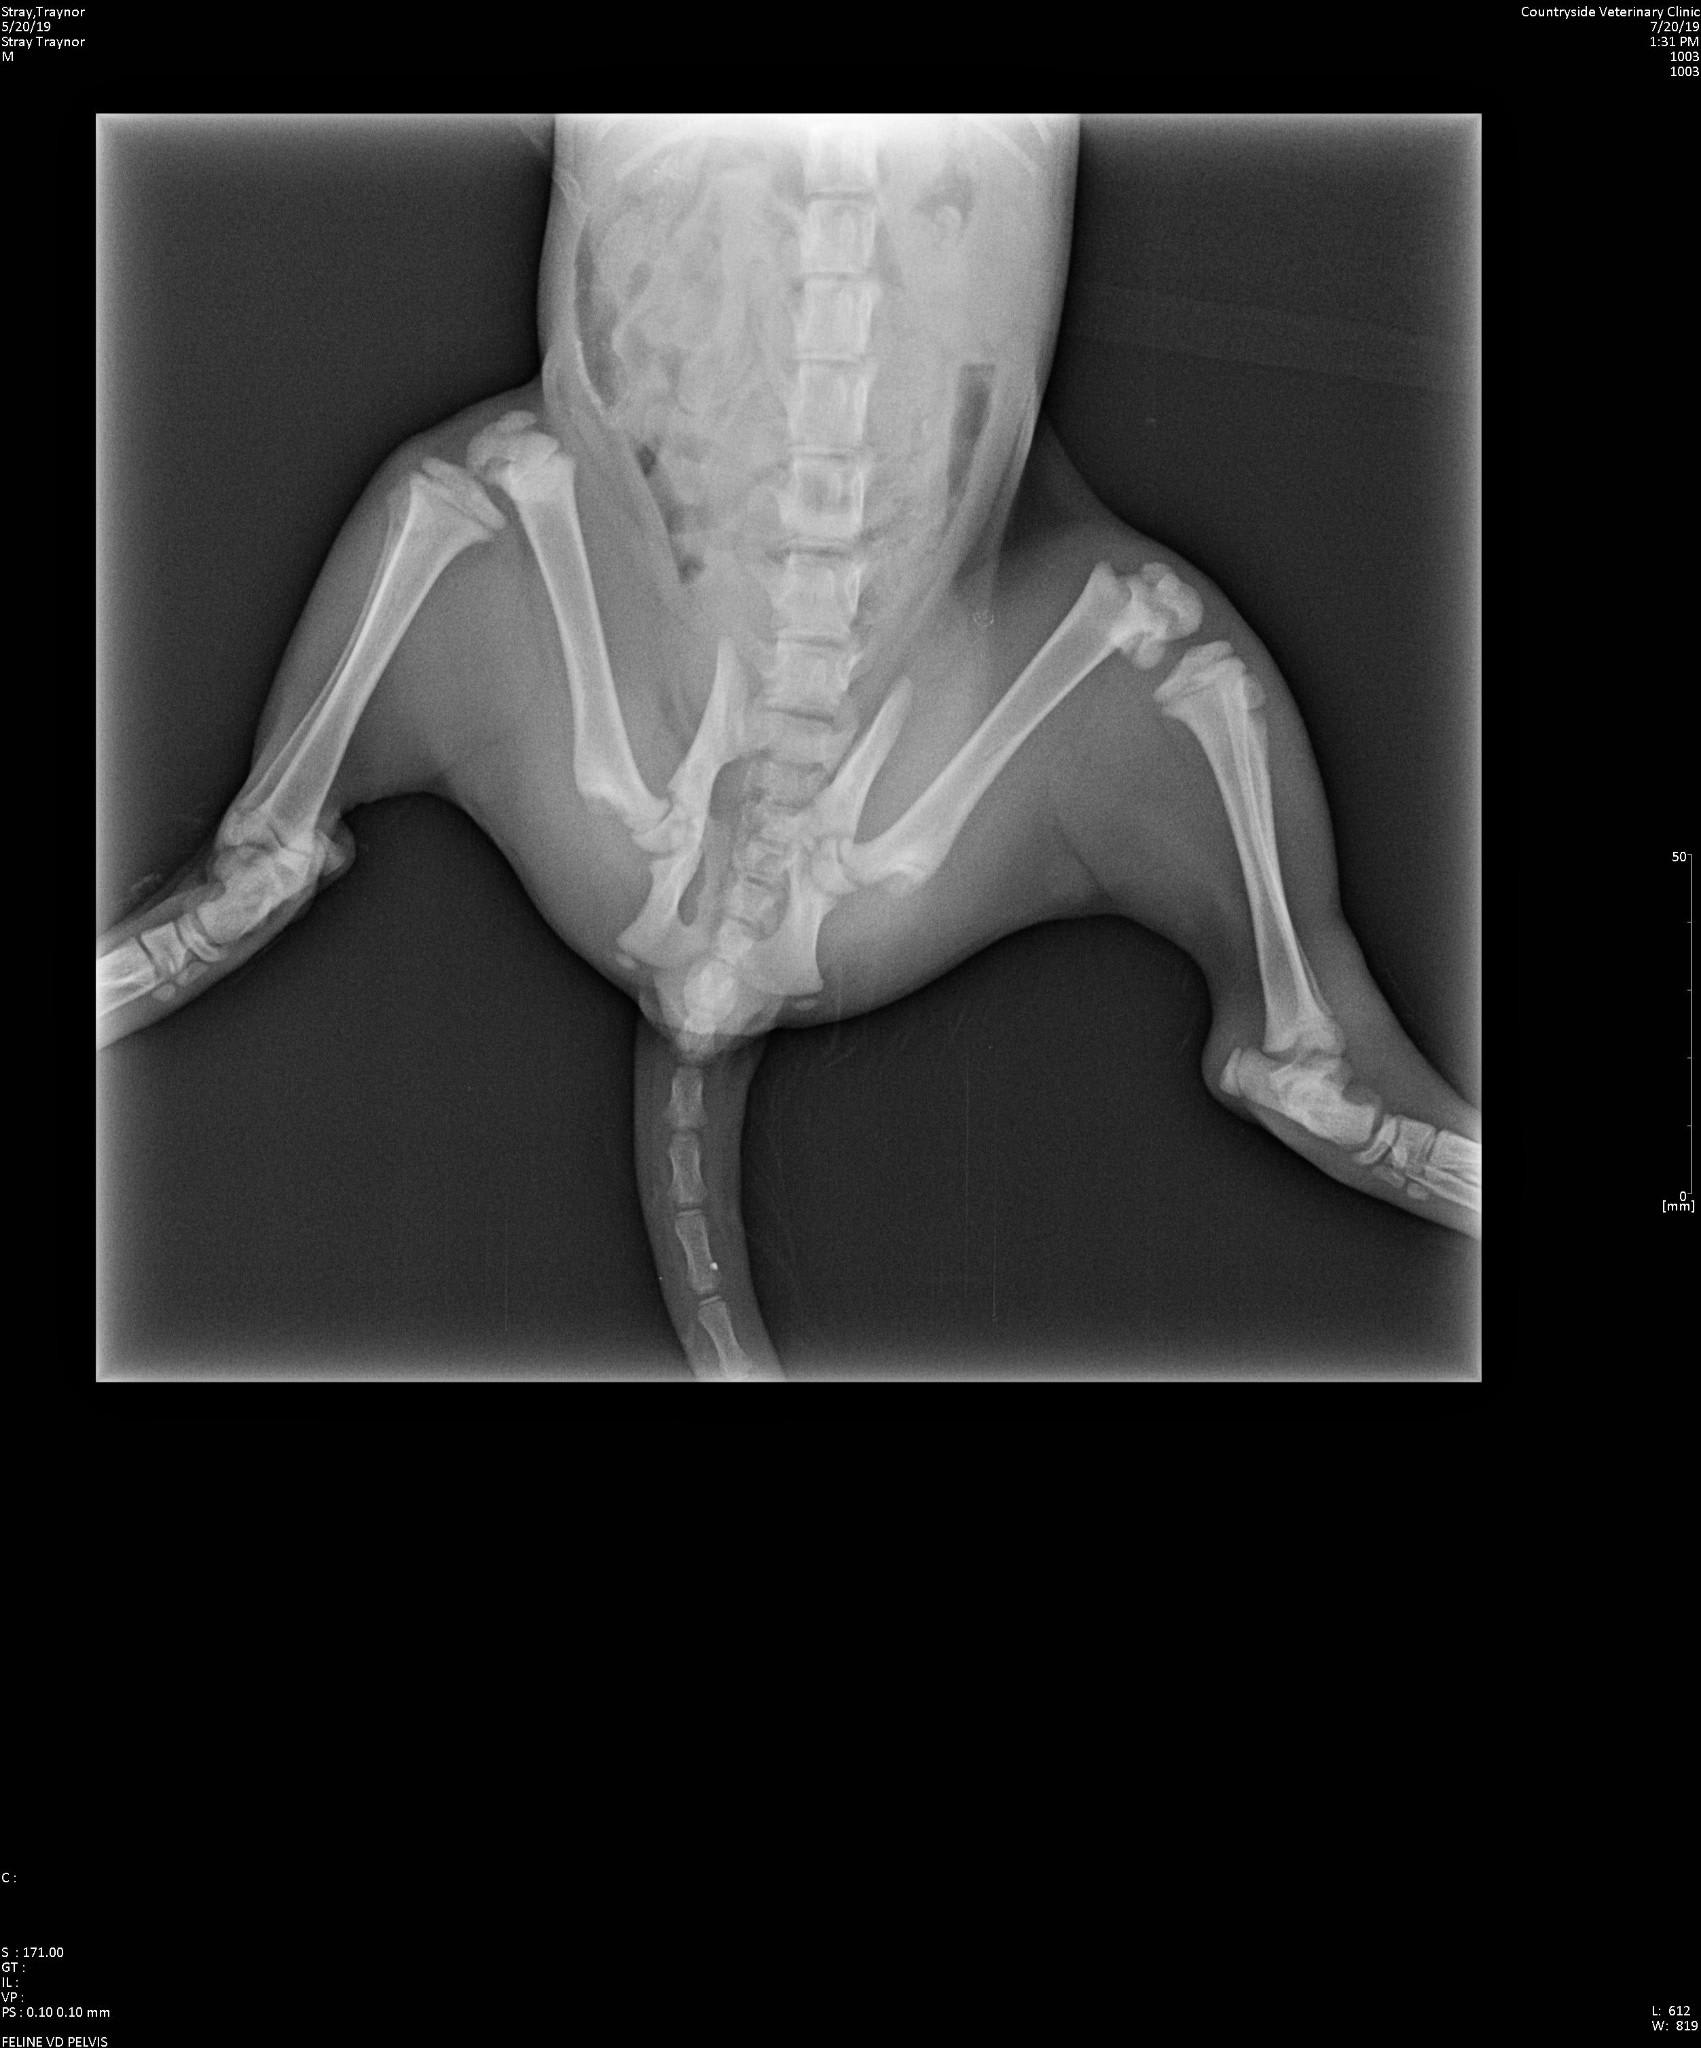

Yesterday we found a kitten with a broken leg and a fractured pelvis. The vet took X-rays and saw no sign of internal bleeding. However there is blood when he pees. What could be causing this?

Poor Otis. I recommend to have Otis examined by the veterinarian again today. Sometimes the bladder can be injured or even ruptured and the blood could be related to that and may need to be addressed quickly. The doctor may need to take another radiograph to check for a bladder rupture. I hope he gets better quickly and please feel free to post any additional questions.